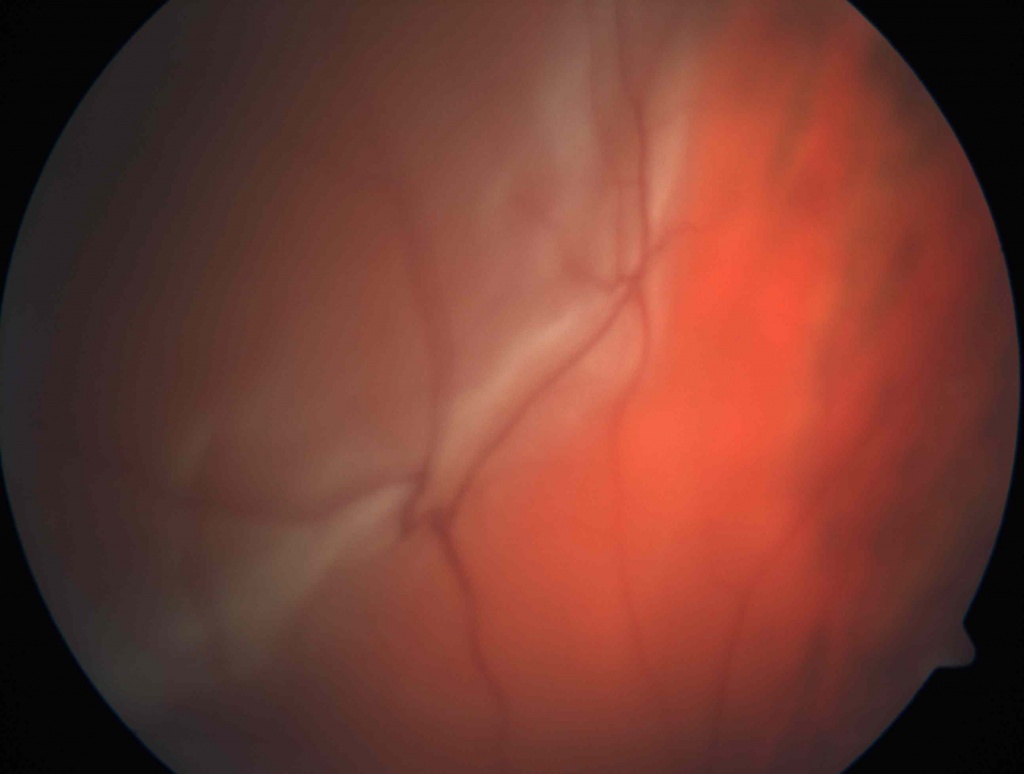

Отслойка сетчатки -патологическое состояние глаза,которое нуждается в срочном оперативном лечении, так как это заболевание приводит к достаточно быстрой полной потере зрения. Отслойки могут быть регматогенными- в результате образования разрыва сетчатки, как правило после трав и при близорукости; тракционными, возникающих после гемофтальмов и экссудативными при воспалительных заболеваниях и при опухолях сосудистой оболочки. Предвестниками отслойки сетчатки могут быть появление вспышек, искр, плавающих точек, что может указывать на образование разрыва сетчатки. Эти жалобы служат поводом для обращения к офтальмологу, так как на данном этапе возможно остановить развитие отслойки сетчатки при помощи лазеркоагуляции сетчатки. Далее появляются жалобы на снижение зрения и возникновение «занавески» перед глазом. Это признаки уже начавшейся отслойки сетчатки. Хирургическое лечение- единственный метод лечения при отслойке сетчатки. Витрэктомия - одно из самых сложных оперативных вмешательств в офтальмологии. Как правило, операции при отслойке сетчатки многоэтапные с применение вводимых в полость стекловидного тела перфтора и силиконового масла, одномоментной эндолазерлазеркоагуляцией. Реже выполняются эписклеральные операции.

Периферические дистрофии сетчатки (ПХРД и ПВХРД) – это заболевания дистальных отделов сетчатки, связанное с нарушением кровоснабже-ния в локальных участках периферии сетчатки, что приводит к нарушению обмена веществ и к появлению истончения сетчатки. Воспалительные забо-левания глаз, травмы головы и глаза, атеросклероз и гипертоническая болезнь, наследственный фактор, интоксикация, физические нагрузки могут быть причиной развития дистрофии сетчатки. При близорукости в виду увеличенного размера глазного яблока оболочки растянуты, истончены и дистрофия встречается чаще. Как правило, периферические дистрофии об-наруживаются при осмотрах пациентов с широким зрачком, так как забо-левание протекает практически бессимптомно. Иногда пациенты жалуются на появление «мушек» и вспышек перед глазами. Не выявленные вовремя дистрофии могут привести к развитию отслойки сетчатки. При выявлении периферической дистрофии и разрывов сетчатки проводят лечение, целью которого является профилактика отслойки сетчатки. Выполняют профи-лактическую лазерную коагуляцию сетчатки в области дистрофических изменений или отграничивающую лазерную коагуляцию вокруг уже существующего разрыва.